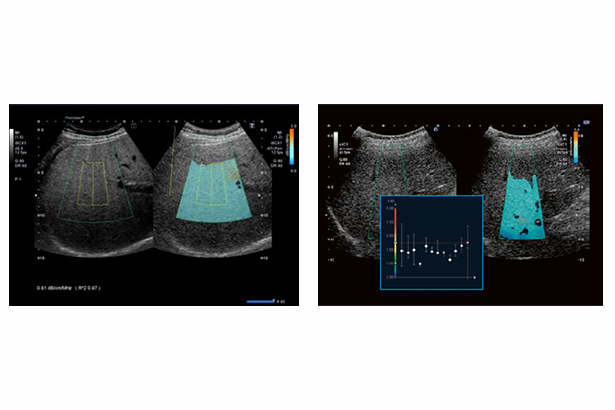

ATI可以測量組織中超聲波衰減的程度,對脂肪變程度進行量化。它可以自動消除腹壁處產生的噪聲,成像質量更佳。新的趨勢圖可以幫助監控疾病進程和隨訪。